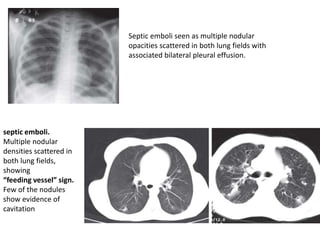

Septic emboli seen as multiple nodular

opacities scattered in both lung fields with

associated bilateral pleural effusion.

septic emboli.

Multiple nodular

densities scattered in

both lung fields,

showing

“feeding vessel” sign.

Few of the nodules

show evidence of

cavitation